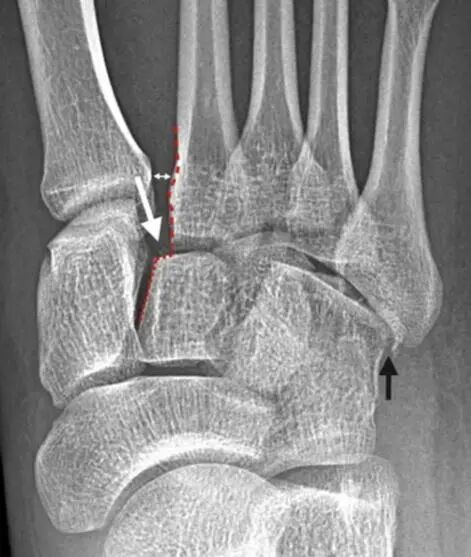

Lisfranc 韧带损伤分级

一级损伤:Lisfranc 韧带扭伤,在负重位片上正侧位均无明显改变,骨间隙无明显扩张、足弓高度没有下降,但骨显像信号增加。

二级损伤:Lisfranc 韧带断裂,第 1、2 跖骨间隙 1~5 mm,足弓高度没有下降。

三级损伤:第 1、2 跖骨骨间隙明显增宽,足弓高度下降(第五跖骨骨足底面之间的距离)。